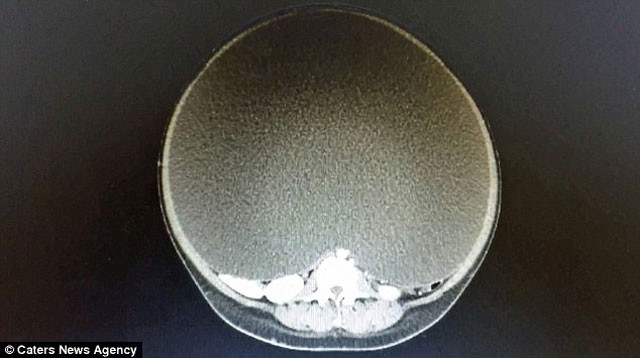

11 aydır büyüyen kitle, operasyonla alınana kadar 33 kiloya ulaşmıştı. Kalp krizi riskiyle karşı karşıya olan kadının iç organları ciddi oranda hasar görmüştü.

Operasyonu gerçekleştiren Dr. Erik Hanson Viana, 10 yeni doğmuş bebek ağırlığında olan kistin hayatında gördüğü en büyük kist olduğunu söyledi.

Kitle genç kadının karnının %95'ini kaplıyordu. Kitlenin çevresi 157 cm iken boyu yarım metreyi buluyordu.